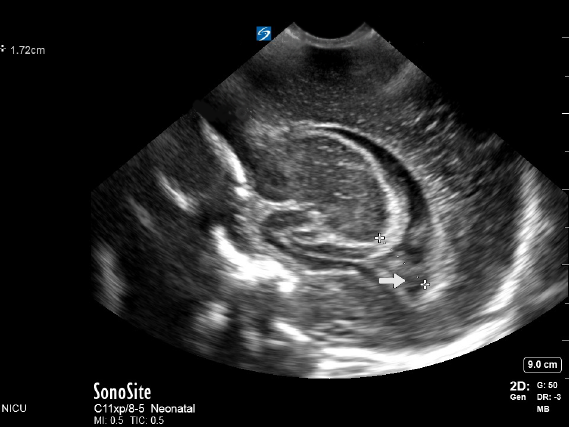

Neonatology TOD 2 Image